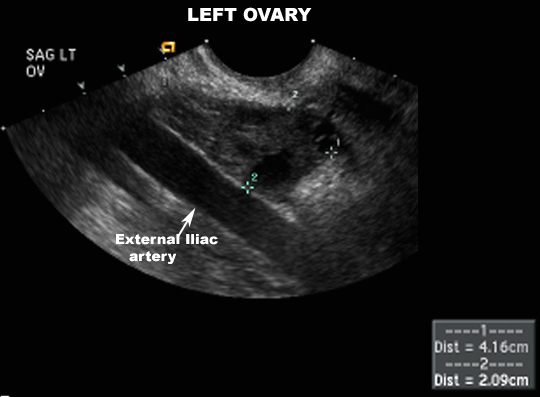

US Pelvis |